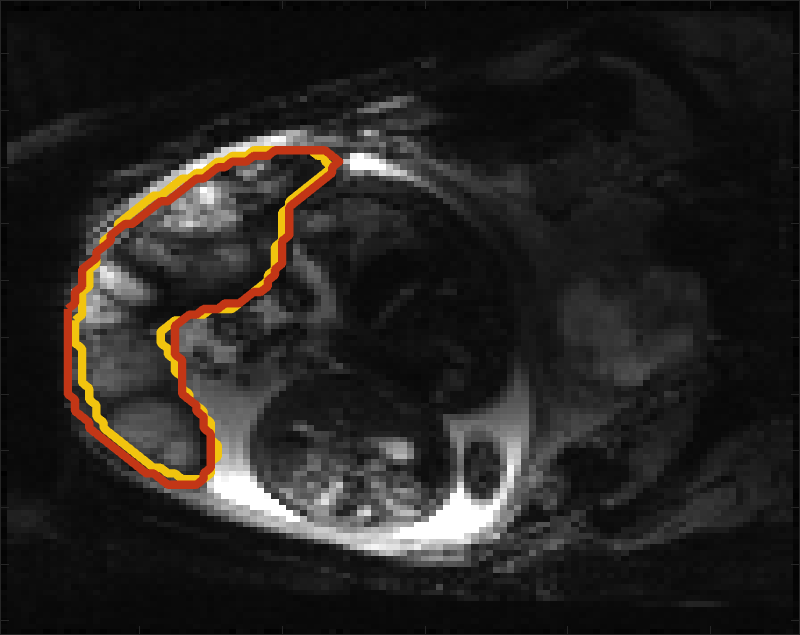

Despite its importance for many downstream clinical research tasks, placental segmentation is often performed manually and can take a significant amount of time, even for a trained expert. For BOLD MRI studies, manual segmentation is rendered more challenging due to the sheer number of MRI scans acquired and rapid signal changes due to the experimental design. Experiments acquire several hundred whole-uterus MRI scans to observe signal changes in three stages: i) normoxic (baseline), ii) hyperoxic, and iii) return to normoxic. During the hyperoxic stage, the BOLD signals increase rapidly, leading to hyperintensity throughout the placenta. Furthermore, the placental shape can undergo large deformation caused by maternal breathing, contractions, and fetal motion which can be particularly increased during hyperoxia [25]. See Fig. 1 for two examples.

Fig 3 compares the predicted label maps with ground truth on subjects with increasing Dice scores using the BW-CE model. The model accurately identifies the location of the placenta, but in the worst cases misses boundary details.